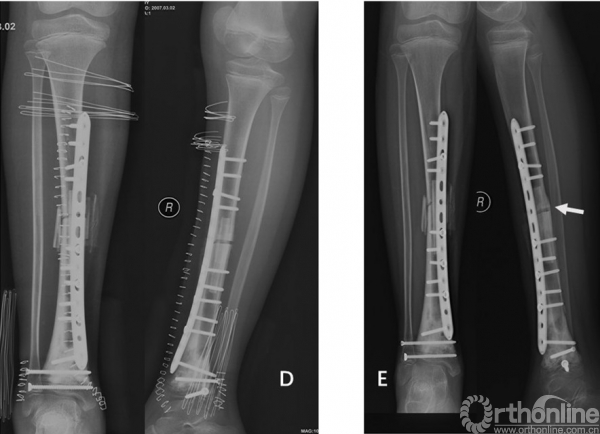

图1女性/9岁,右胫骨下端骨肉瘤。A术前X光片,右胫骨下端骨肉瘤。B化疗后MRI显示软组织包块消失,病变局限于骨内。C术中完整切除胫骨远端肿瘤后刮除髓腔内肿瘤、65℃ 20%高渗盐水灭活30分钟后原位回植、对侧自体腓骨置于髓腔中心、钢板内固定、LARS韧带重建内踝软组织、下胫腓关节融合。D术后即刻X光片。E术后4个月X光片显示截骨面已愈合。F术后踝关节功能良好,4个月后无需支具辅助可正常行走。